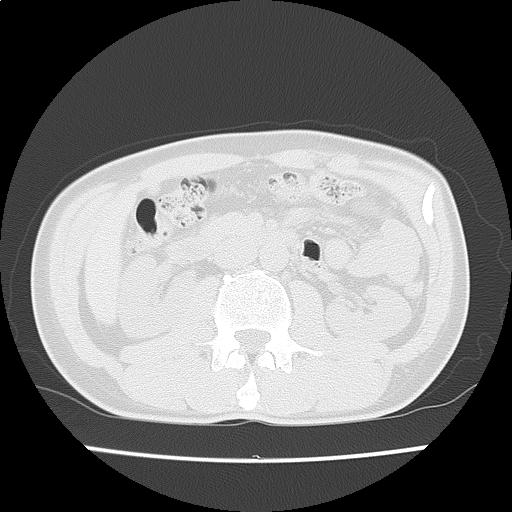

【読影指南】症例画像6

右肺に斑状影・粒状影を認める。フォロー。背部痛もあり

年齢: 53歳

性別: 男性

検査部位: 胸腹部

検査種別: CT

CTスライス画像

CTスライス1